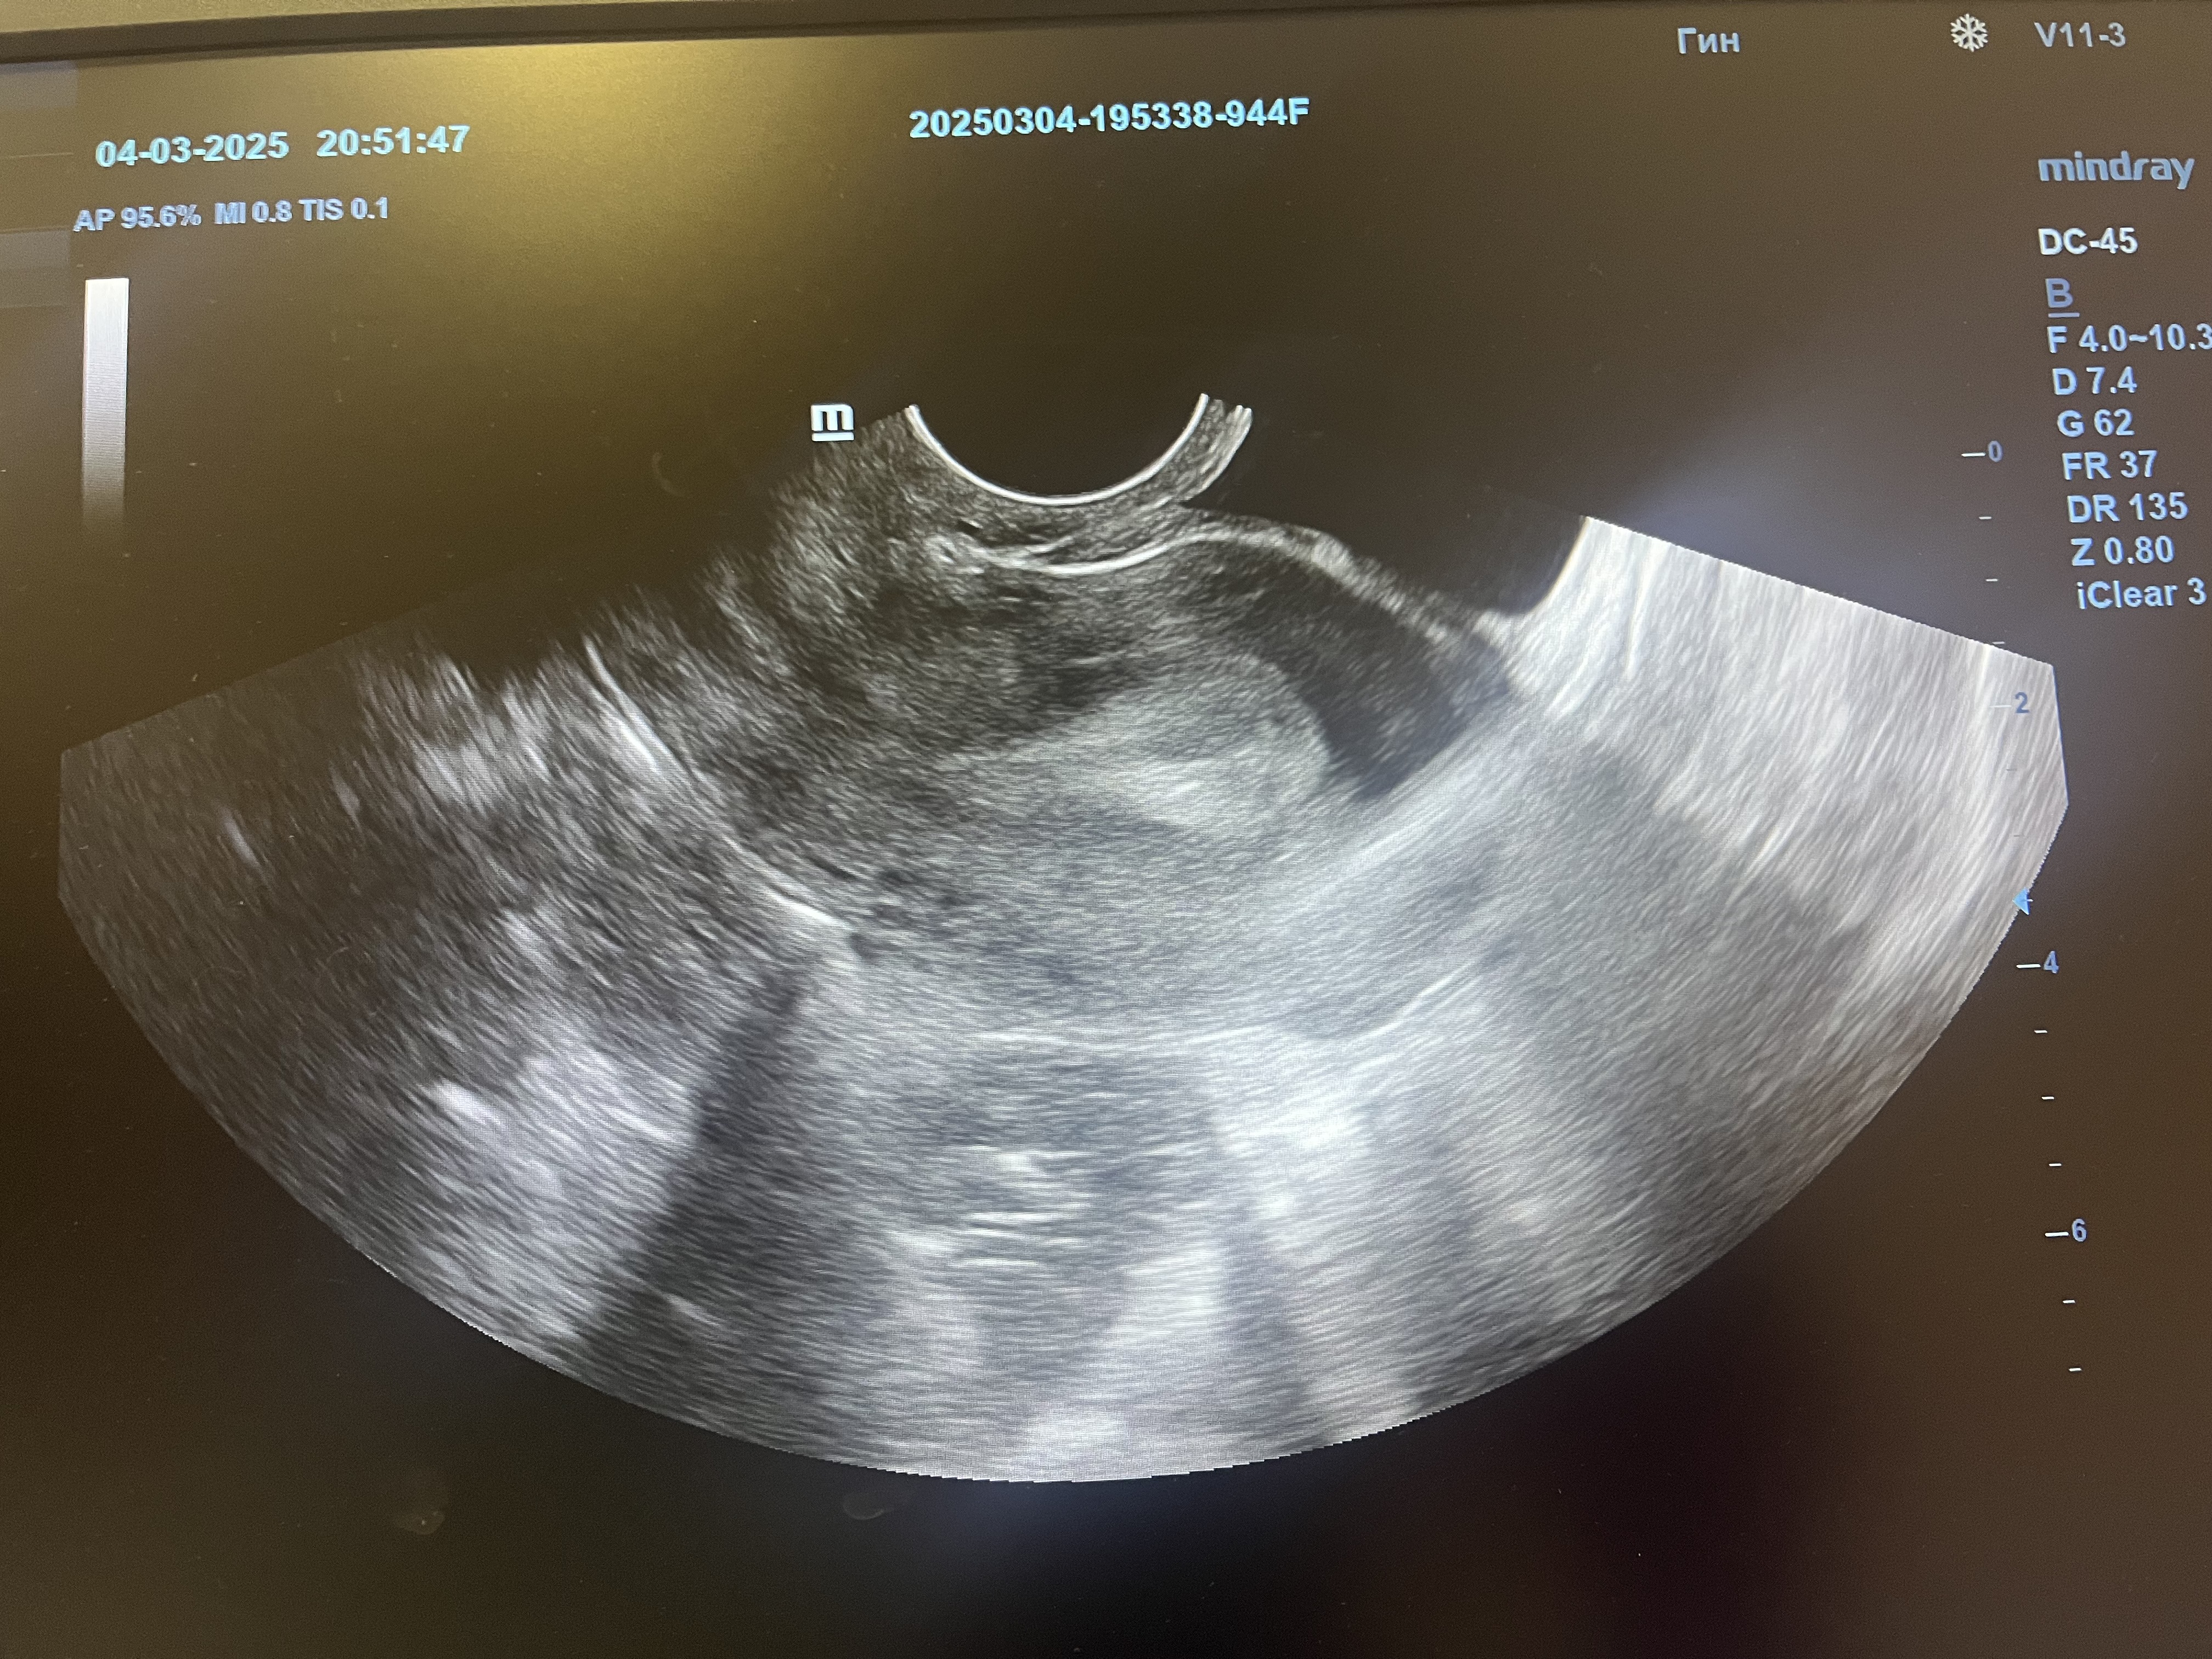

УЗИ, мультифолликулярные яичники

Планирую, жалобы на тянущие боли внизу живота, 22 ДЦ, тесты отрицательные, овуляцию она не увидела, сказала что мелкие фолликулы и эндометрий 14мм, и видит что то в полости, но не думает что это плодное яйцо,поставили Мульти.Ф.Яичники, девочки гляньте, так переживаю, в этом месяце новый здоровый партнер, до этого ни разу не говорили про это диагноз.

примерно 6-8 ДПО